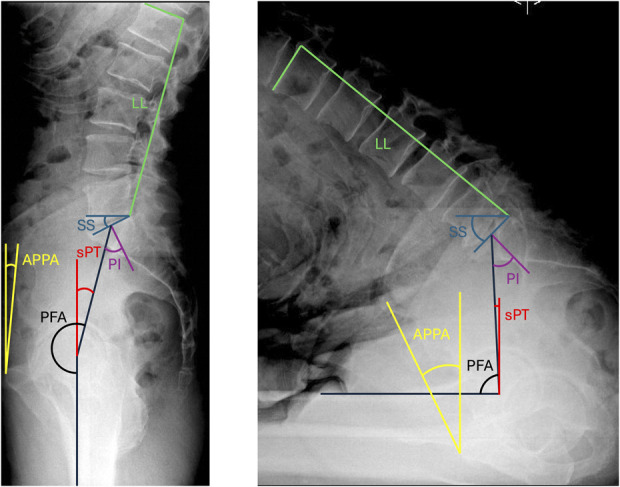

Methods: A prospective database was queried to identify patients with adverse (n = 70) spinopelvic characteristics. These were matched for age and sex with patients without adverse characteristics (n = 70). Spinopelvic characteristics were obtained from radiographs and computed tomography (CT) scans. CT scans were segmented to determine native acetabular anatomy, particularly anteversion. Three hip-spine planning algorithms were evaluated for each patient (Optimized Positioning System [OPS], Combined-Sagittal Index [CSI], Hip-Spine Classification). Differences between target orientations and native anatomy were determined. Agreement between algorithms was tested.